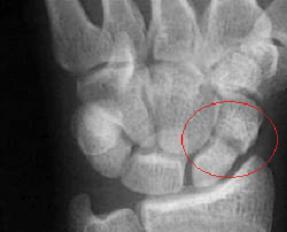

Scaphoid Fractures

Scaphoid fractures account for almost 75% of all broken carpal bones in the hand. This bone is also known as the “navicular” bone; one of the small bones in the hand and sits between the base of the thumb and the second metacarpal bone.

Diagnosis can be a difficult task at times. Aside from obvious findings on x-rays, sometimes multiple resources are necessary to identify and verify the presence of the break, such as MRI examination, Bone Scans and "blood flow" studies of the bone to determine if the injured bone is indeed receive adequate blood supply.